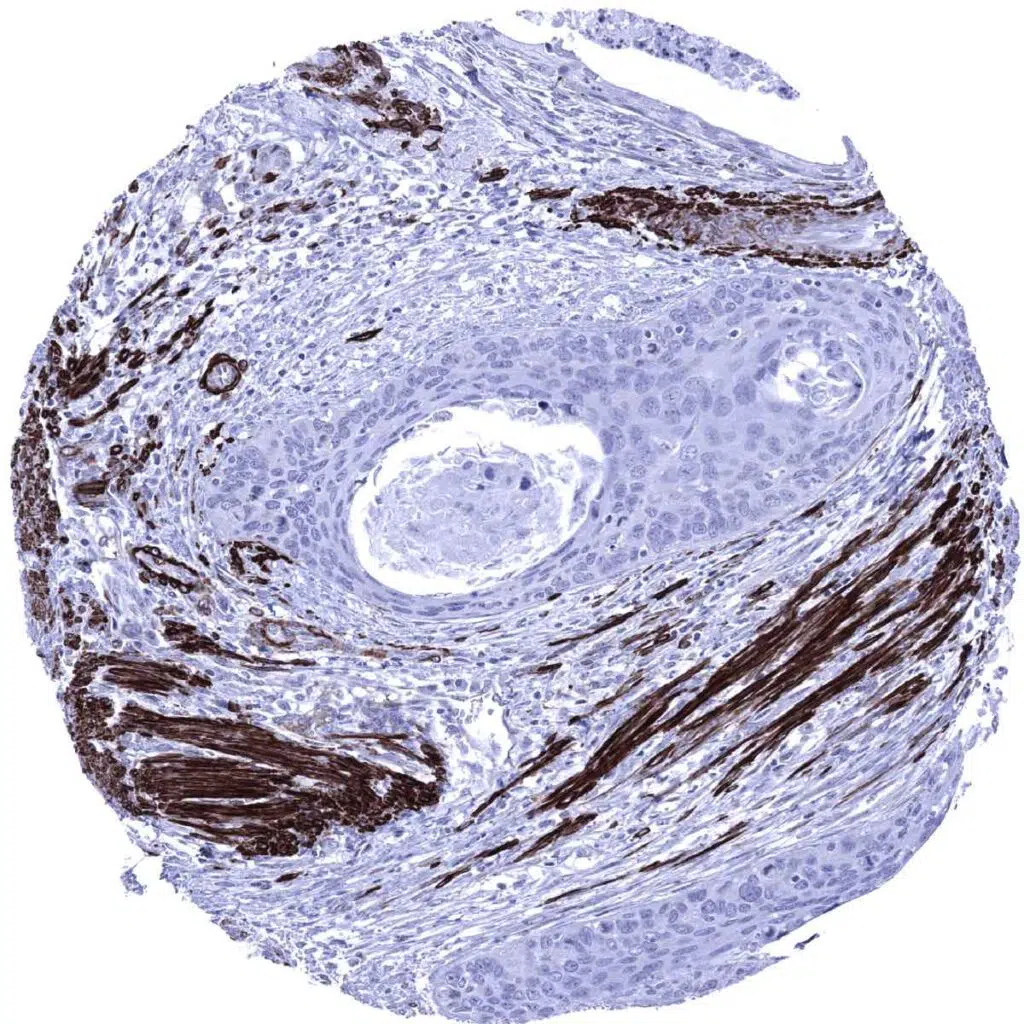

Prostate- Caldesmon negative adenocarcinoma (Gleason 3+3=6) surrounded by prostatic stroma rich in caldesmon positive smooth muscle cells (Caldesmon immunohistochemistry).